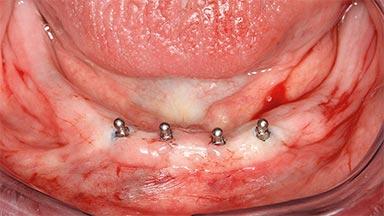

Four Immediately Loaded Mini-Implants Supporting a Mandibular Overdenture

# of Implants 4

Type of Implants One-Piece|Reduced-Diameter

Defining Characteristics Fully edentulous lower jaw to be rehabilitated with two or more implants

Modality 3 or 4 interforaminal implants